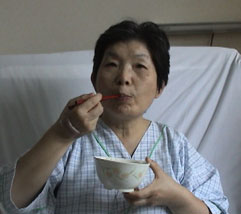

数時間後、ようやく痛みも治まり、笑顔が・・ |

| さあ、お腹が空いただろう。 |

| 特別室で2日間、14日までいた。 |